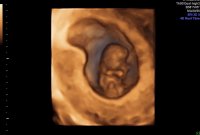

Lille trille vokser videre ❤️ 11+0 i dag, ble målt til 11+2.

Nakkefold er på 1mm, normalgrensen var visst opp til 3,5mm. Sjekket papirene fra sist, og der hadde engel 4mm..

Alt ser bra ut til nå, og utifra hva ultralydjordmor sa, så er alt perfekt denne gangen ❤️ Neste uke blir det mer anatomisk gjennomgang, for da er jeg over i uke 12, men min største milepæl blir å nå 15uker :)